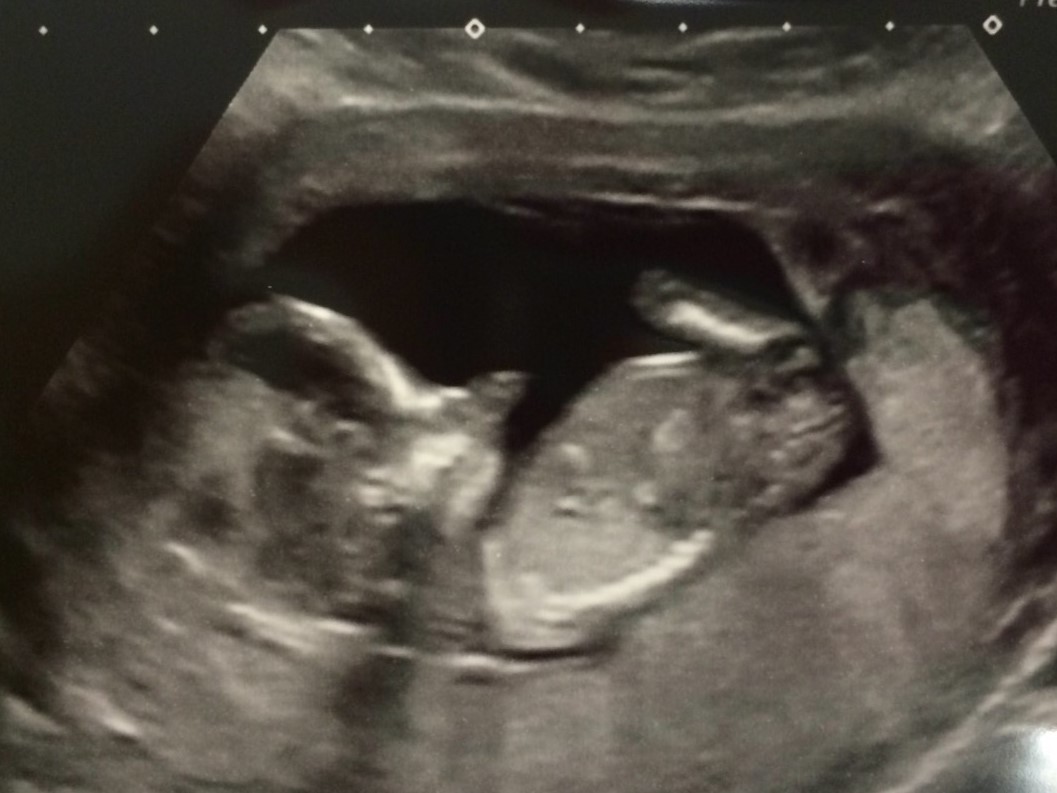

Tricky as there is a little bump above a flat line. The line makes me think girl but the bump might be a scrotal bump. I'm hesitantly girl.

Do you have any others? Not a great view of the nub. How far along are you?